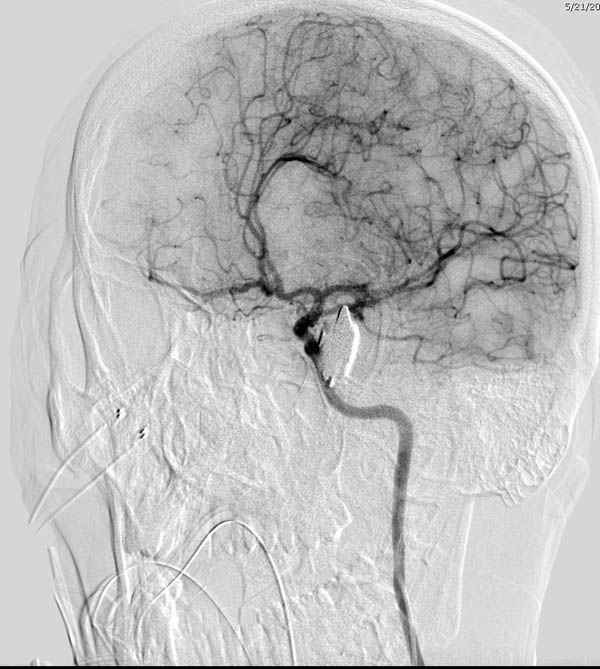

По протоколу сделаны все необходимые исследования: рентген, ангиограмма с 3Д реконструкцией, где обнаружили что все жизненно важные сосуды не задеты, даже некоторые "сидят" изгибаясь на ноже.